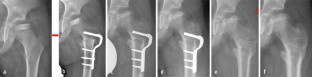

Abb. 1